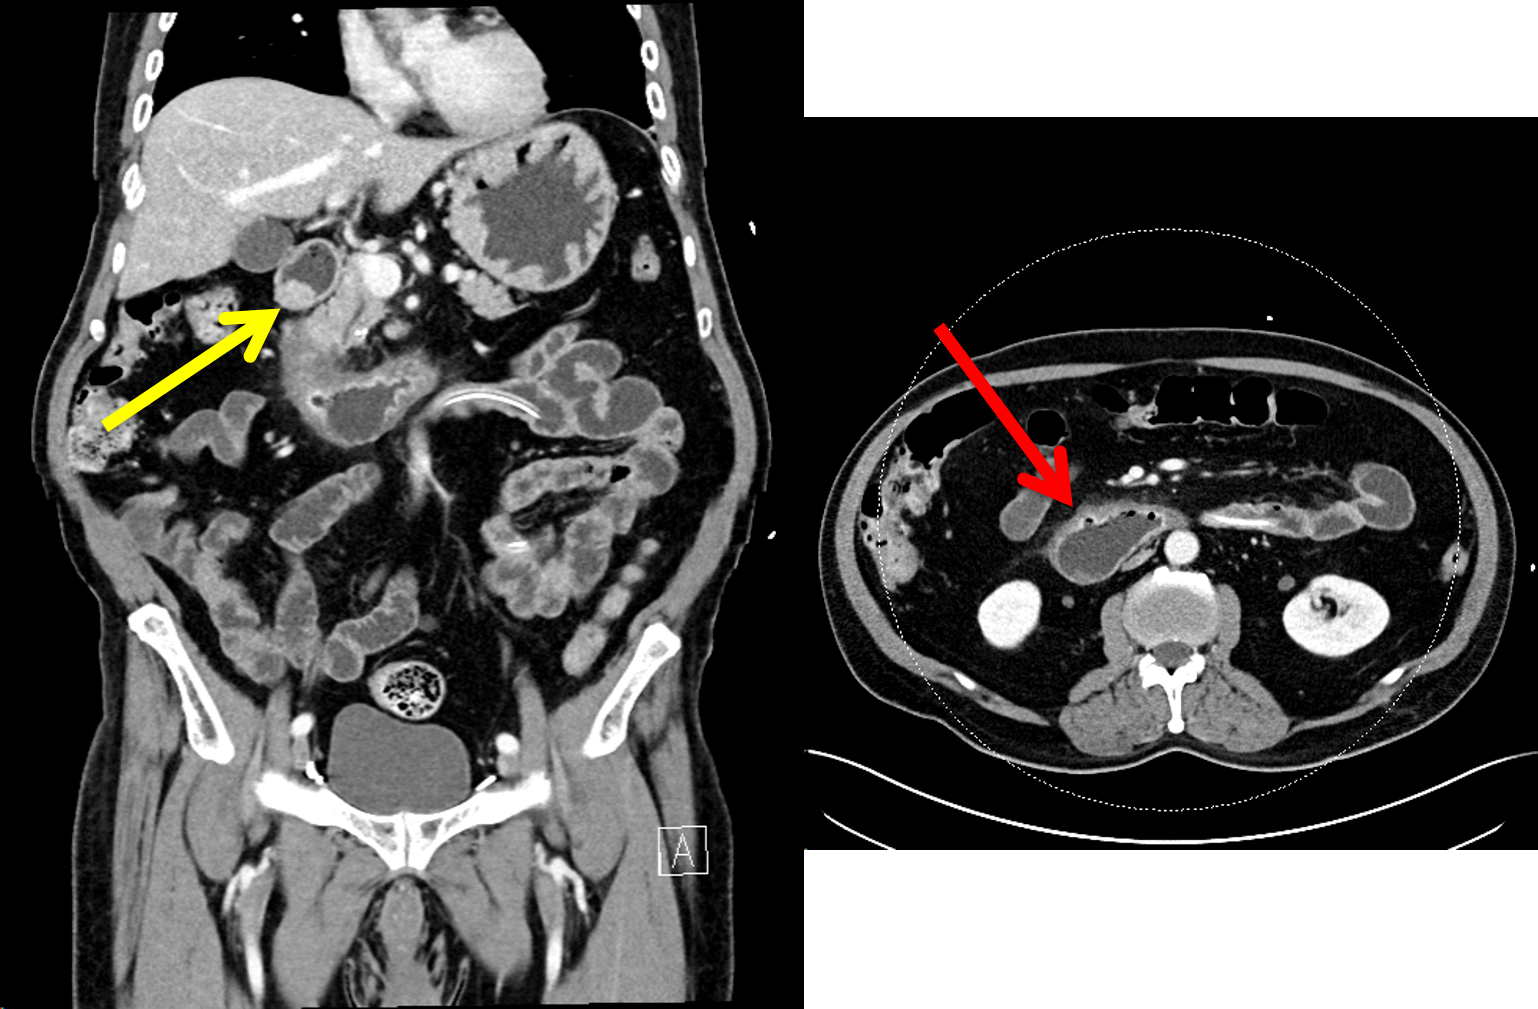

90% of gastrinomas occur in the gastrinoma triangle, which is located between the confluence of the cystic duct and CBD, junction of the 2nd and third portions of the duodenum, and junction of the neck and body of the pancreas.

These highly vascular tumors classically show enhancement on arterial phase.